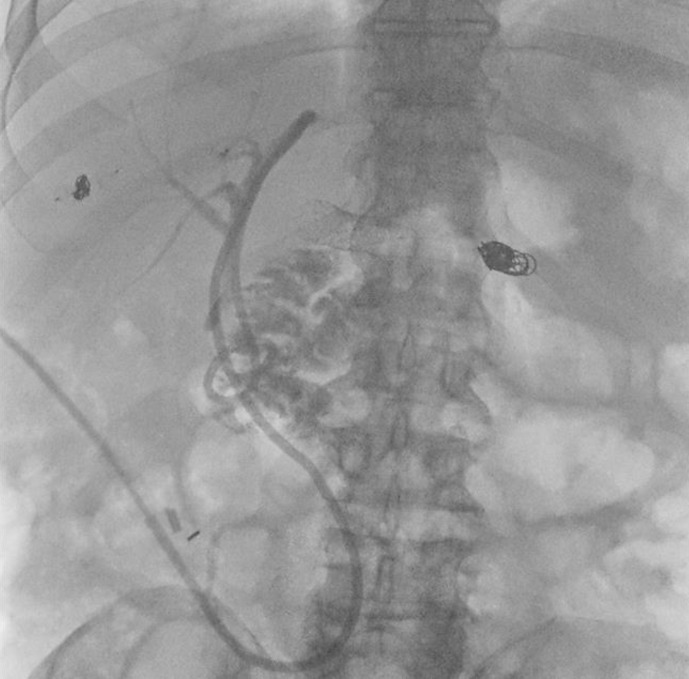

简介:门静脉假性动脉瘤是胰十二指肠切除术后一种罕见但可能危及生命的并发症。我们在此报告这一严重并发症的成功微创治疗:一位 68 岁的男性患者曾在另一家医院接受胰十二指肠切除术和门静脉楔形切除术,因持续胆汁渗漏和间歇性出血来到我科就诊。腹部计算机断层扫描显示,胰空肠造口周围有大量积液,肝总动脉闭塞,门静脉假性动脉瘤。治疗采用了微创方法,包括放置血管内门静脉支架和通过开裂的肝空肠造口进行经皮经肝胆道引流(PTBD)。随后在胰周积液处放置经皮胰尾,以充分引流。放置支架后,抗生素的使用时间共计 6 周。在随后的几周内,PTBD 可以被内化,辫子也可以被移除,之后患者就可以出院了。在门诊就诊时,通过 PTBD 注射造影剂证实没有胆汁渗漏,之后引流管即可拔除:本文介绍了为数不多的已发表的胰十二指肠切除术后门静脉假性动脉瘤病例,并强调了微创血管内支架和 PTBD 置入术在处理这种罕见且可能致命的并发症中的重要作用。

Case presentation: A 68-year-old male patient who had undergone pancreatoduodenectomy with portal vein wedge resection at another facility presented to our department due to persistent bile leakage and intermittent bleeding. Abdominal computed tomography scanning demonstrated a large fluid collection surrounding the pancreatojejunostomy, with an occlusion of the common hepatic artery as well as a portal vein pseudoaneurysm. Treatment was performed by means of a minimally invasive approach, including endovascular portal vein stent placement and percutaneous transhepatic biliary drainage (PTBD) through the dehiscent hepaticojejunostomy. This was followed by the placement of a percutaneous pigtail in the peripancreatic fluid collection for adequate drainage. Antibiotics were administered for a total duration of 6 weeks following stent placement. In the subsequent weeks, the PTBD could be internalized and the pigtail removed, after which patient was discharged. During outpatient visits, a contrast injection through the PTBD confirmed the absence of bile leakage, after which the drain could be removed.